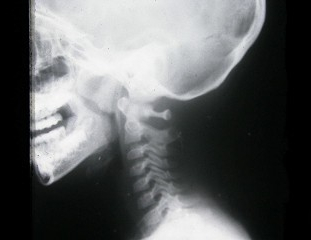

D.肿物内可见空洞

97、单项选择题

男,5岁,反复呛咳,张口呼吸,有鼾声,鼻腔分泌物多。X线检查如图所示,最可能的诊断是()

A.鼻窦炎

B.鼻息肉

C.扁桃体炎

D.腺样体肥大

E.鼻炎